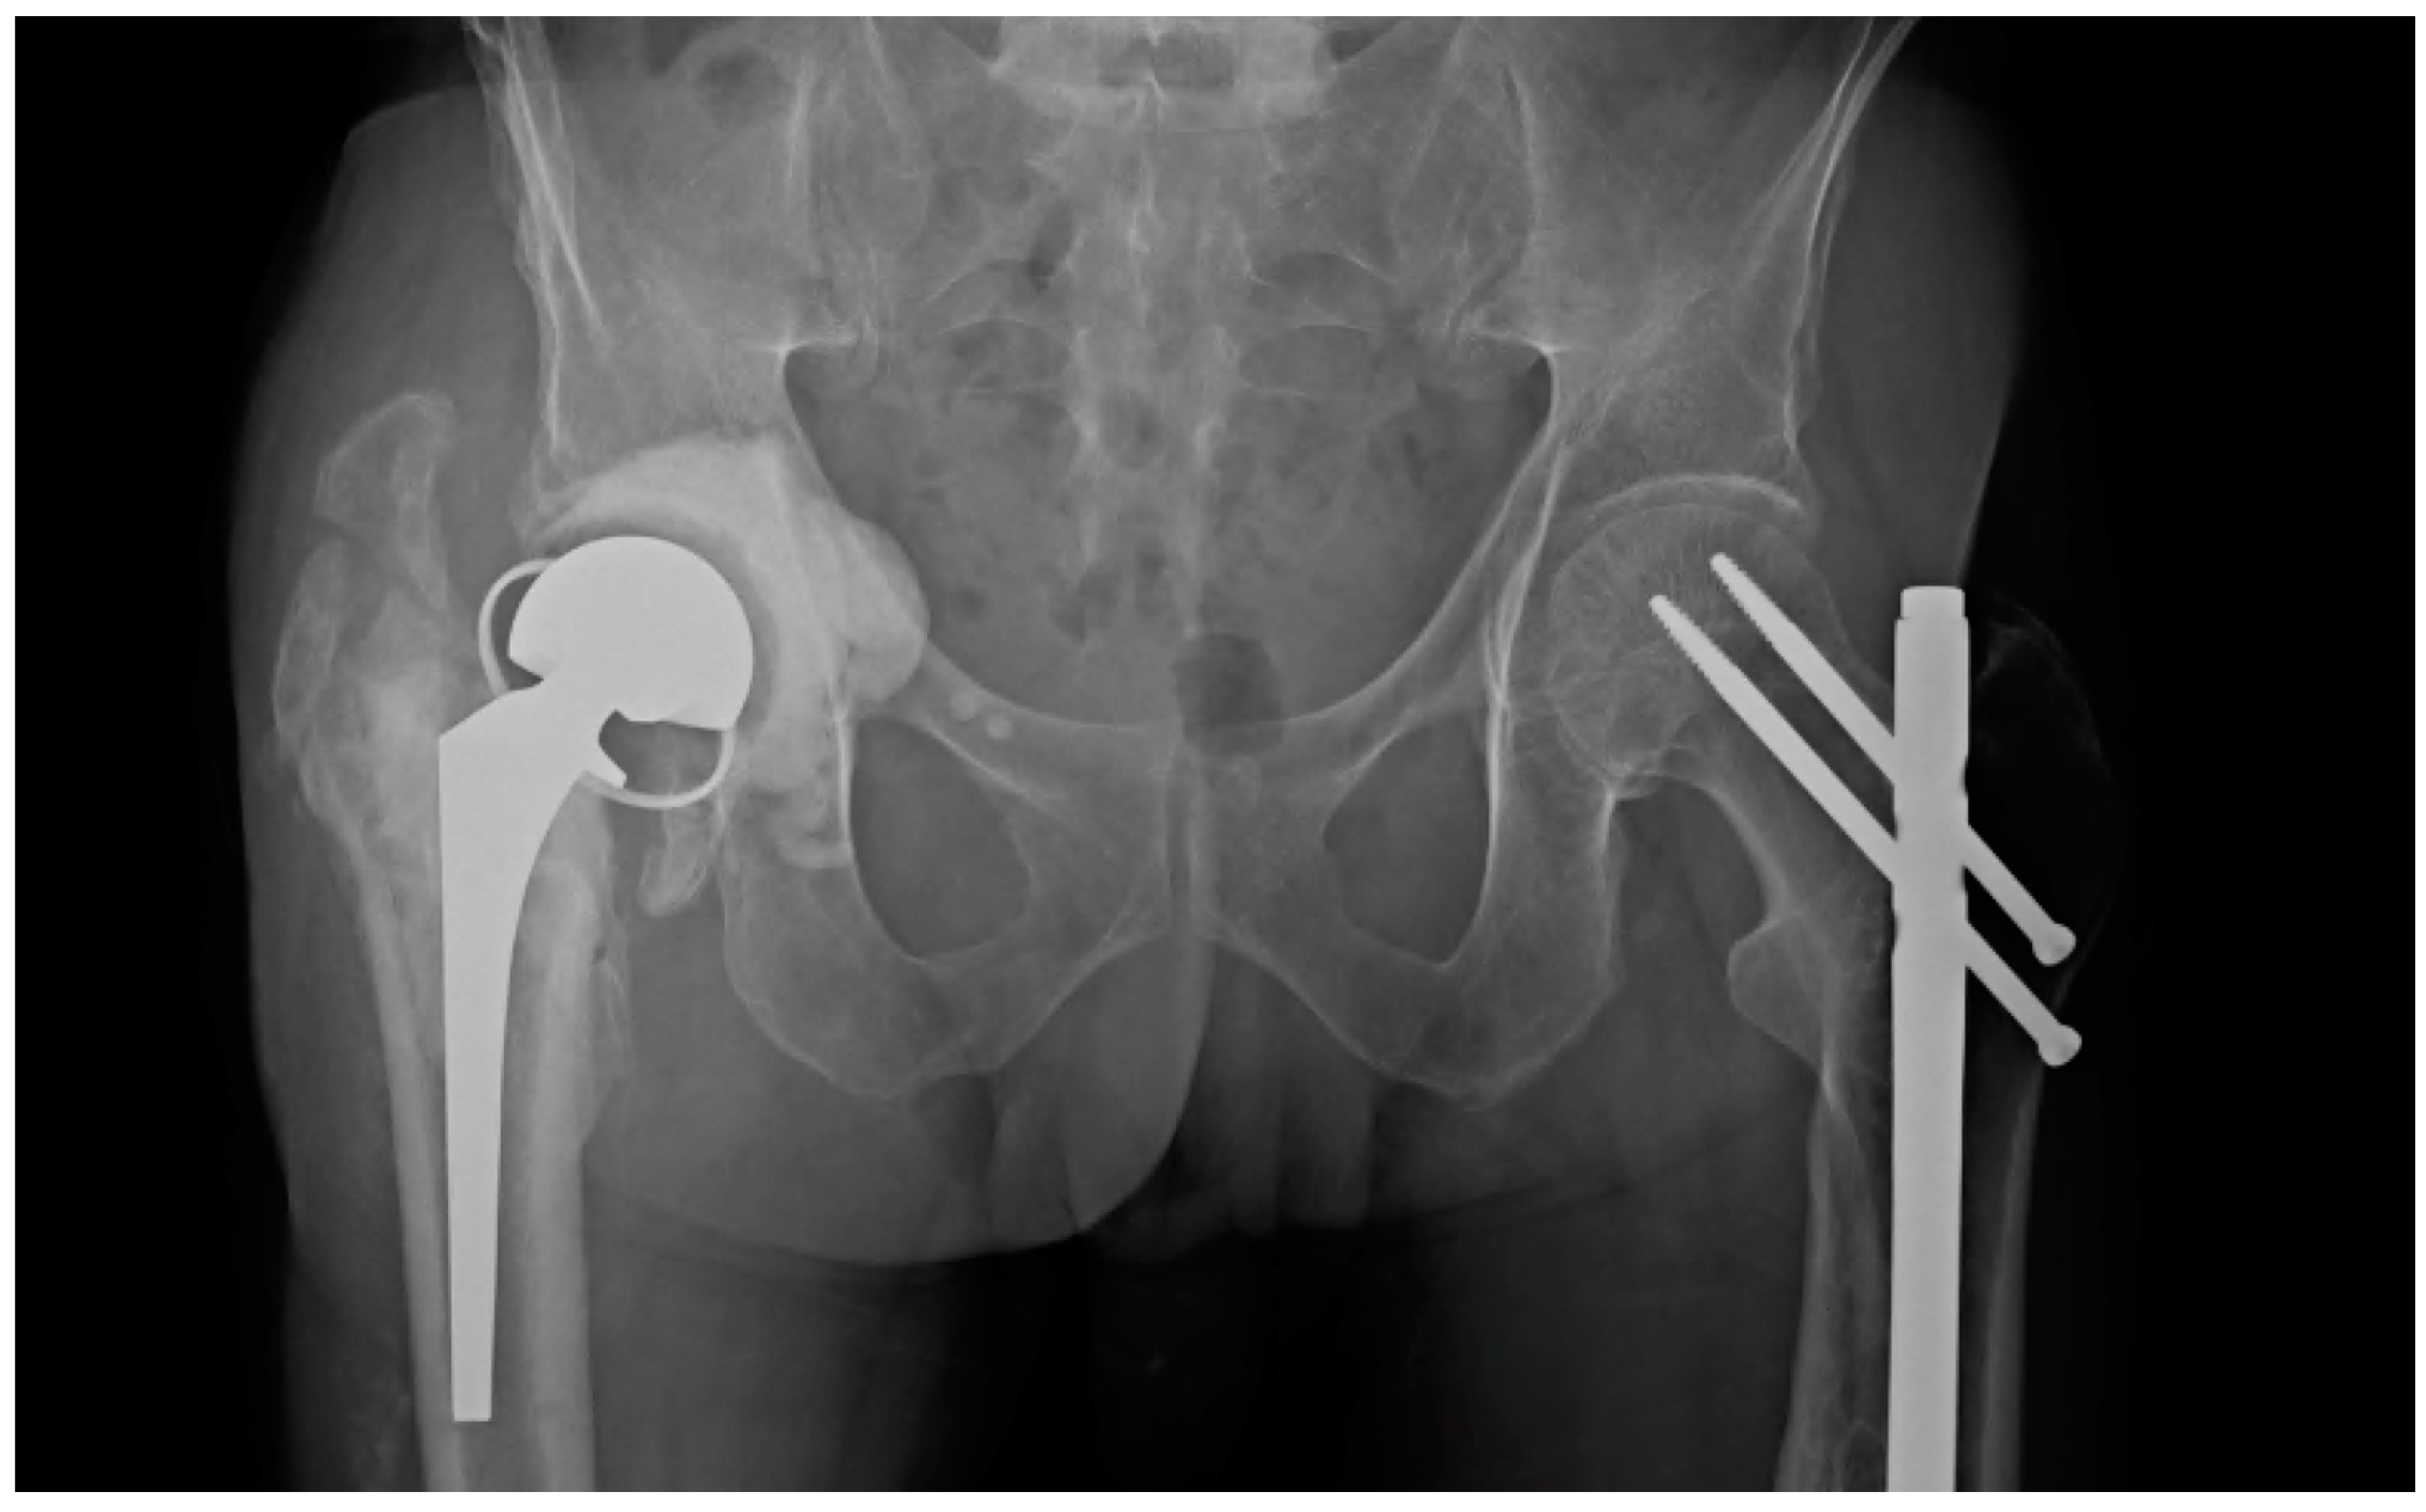

A Modified Cement Spacer Technique for Infected Total Hip

From www.arthroplastyjournal.org

A Modified Cement Spacer Technique for Infected Total Hip Spacers For Hip Replacement two‐stage revision hip arthroplasty is a popular approach for the treatment of late infection after total hip. the following hip spacer guidelines were developed by hss rehabilitation. preformed pmma spacers are also available in various sizes, for both hip and knee surgery, such as the ‘tecres. The use of “functional” spacers may allow patients to return to. Spacers For Hip Replacement.